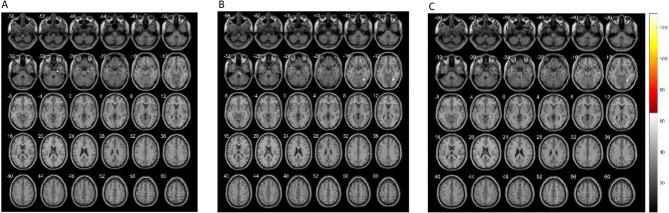

面肌痉挛(HFS)是一种以面部不随意肌肉收缩为特征的慢性神经系统疾病,严重影响患者的生活质量。尽管面神经核与HFS的发病机制有关,但对其在全脑网络中的功能连接的具体研究仍然有限。本研究旨在研究HFS患者在微血管减压(MVD)前后以面神经核为感兴趣区(ROI)的全脑功能连通性的变化,以揭示该疾病的潜在机制和手术干预的影响。对30例HFS患者和30例匹配的健康对照进行静息状态功能磁共振成像(rs-fMRI)。以面神经核为种子ROI分析功能连通性(FC)。收集了人口统计学、临床和实验室数据,包括痉挛严重程度、焦虑和抑郁评分以及术前生物标志物。统计学分析评估了FC的差异及其与临床参数的相关性。与健康对照组相比,HFS患者表现出左侧面部核与右侧海马旁回之间以及右侧面部核与右侧梭状回之间的FC显著增加。这些模式在术后持续存在,在右侧面部核和双侧颞上回之间观察到额外的FC增加。相关分析显示,左侧面核-右侧海马旁回FC与痉挛严重程度和纤维蛋白原水平呈正相关,右侧面核-右侧梭状回FC与单胺氧化酶(MAO)水平呈负相关。术前HFS患者与健康对照组颜面核ReHo差异有统计学意义,而ALFF/fALFF和颜面核偏侧无统计学意义。这项研究强调了面部核与涉及记忆、情感和视觉处理的大脑区域之间FC的改变在HFS发病机制中的作用。虽然MVD可以缓解症状,但其对FC的短期影响似乎有限,这表明功能连接的改变是慢性的,可以作为疾病监测的生物标志物。这些发现为HFS的神经机制提供了新的见解,并强调了对术后长期脑网络适应的进一步研究的必要性。

Hemifacial spasm (HFS) is a chronic neurological disorder characterized by involuntary muscle contractions of the face, significantly impacting patients' quality of life. Although the facial nerve nucleus has been implicated in HFS pathogenesis, specific research on its functional connectivity within whole-brain networks remains limited. This study aimed to investigate alterations in whole-brain functional connectivity with the facial nerve nucleus as the region of interest (ROI) in HFS patients, before and after microvascular decompression (MVD), to uncover potential mechanisms underlying the disorder and the impact of surgical intervention. Resting-state functional magnetic resonance imaging (rs-fMRI) was conducted on 30 HFS patients and 30 matched healthy controls. Functional connectivity (FC) was analyzed using the facial nerve nucleus as the seed ROI. Demographic, clinical, and laboratory data were collected, including spasm severity, anxiety and depression scores, and preoperative biomarkers. Statistical analyses assessed differences in FC and its correlation with clinical parameters. HFS patients demonstrated significantly increased FC between the left facial nucleus and the right parahippocampal gyrus, as well as between the right facial nucleus and the right fusiform gyrus, compared to healthy controls. These patterns persisted postoperatively, with additional increased FC observed between the right facial nucleus and bilateral superior temporal gyri. Correlation analyses revealed that left facial nucleus-right parahippocampal gyrus FC was positively associated with spasm severity and fibrinogen levels, while right facial nucleus-right fusiform gyrus FC was negatively correlated with monoamine oxidase (MAO) levels. ReHo of both facial nucleus showed significant differences between preoperative HFS patients and healthy controls, whereas ALFF/fALFF and lateralisation of facial nucleus did not show significant between-group differences. This study highlights the role of altered FC between the facial nucleus and brain regions involved in memory, emotion, and visual processing in HFS pathogenesis. While MVD provides symptomatic relief, its short-term effects on FC appear limited, suggesting that functional connectivity changes are chronic and may serve as biomarkers for disease monitoring. These findings provide novel insights into the neural mechanisms of HFS and emphasize the need for further research on long-term brain network adaptations post-surgery.